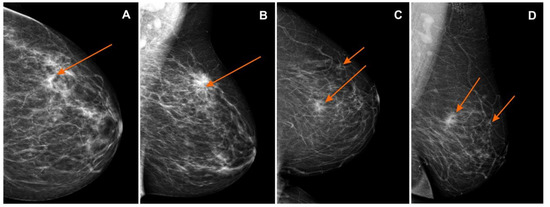

Figure 2. Mammography (MG): (A) craniocaudal (CC) and (B) mediolateral oblique (MLO) views—pathological mass in the left breast in the superior-outer quadrant (orange arrows), invasive lobular carcinoma GII, BI-RADS 6; (C) craniocaudal (CC) and (D) mediolateral oblique (MLO) views—pathological mass in the left breast in the superior-inner quadrant (orange arrows), infiltrating duct carcinoma, BI-RADS 6. BI-RADS: Breast Imaging-Reporting and Data System.